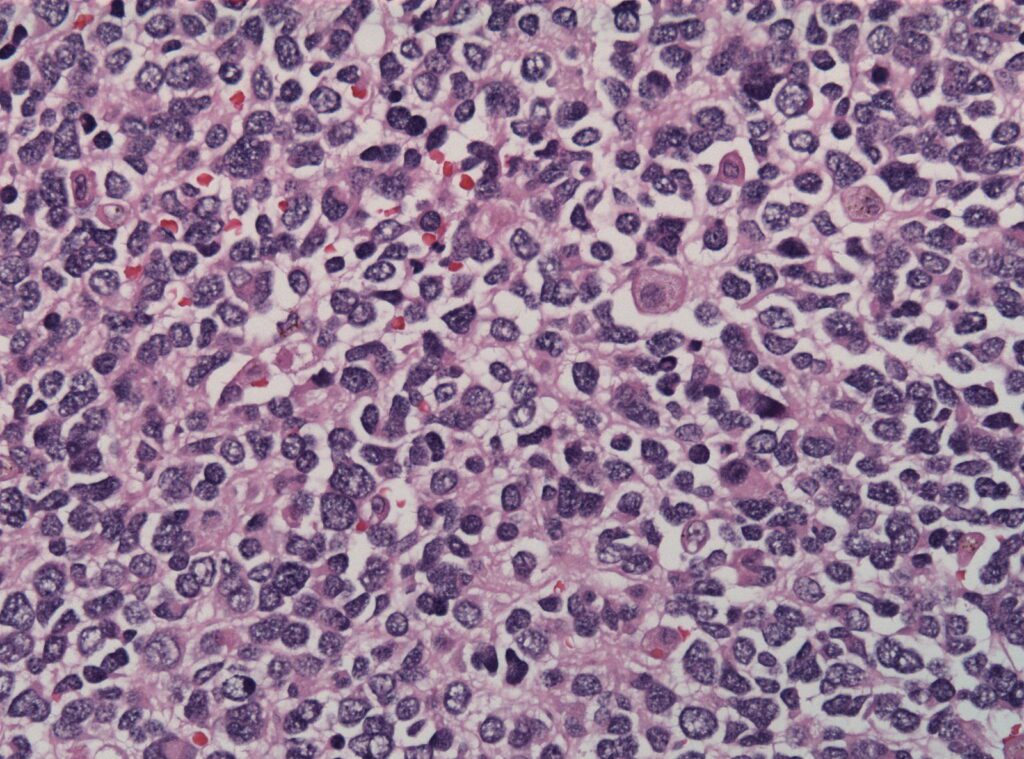

[3]Image credit: https://commons.wikimedia.org/wiki/File:Pheochromocytoma_high_mag.jpg

[4]Image credit: https://commons.wikimedia.org/wiki/File:Neuroblastoma_cell_matruration.jpg